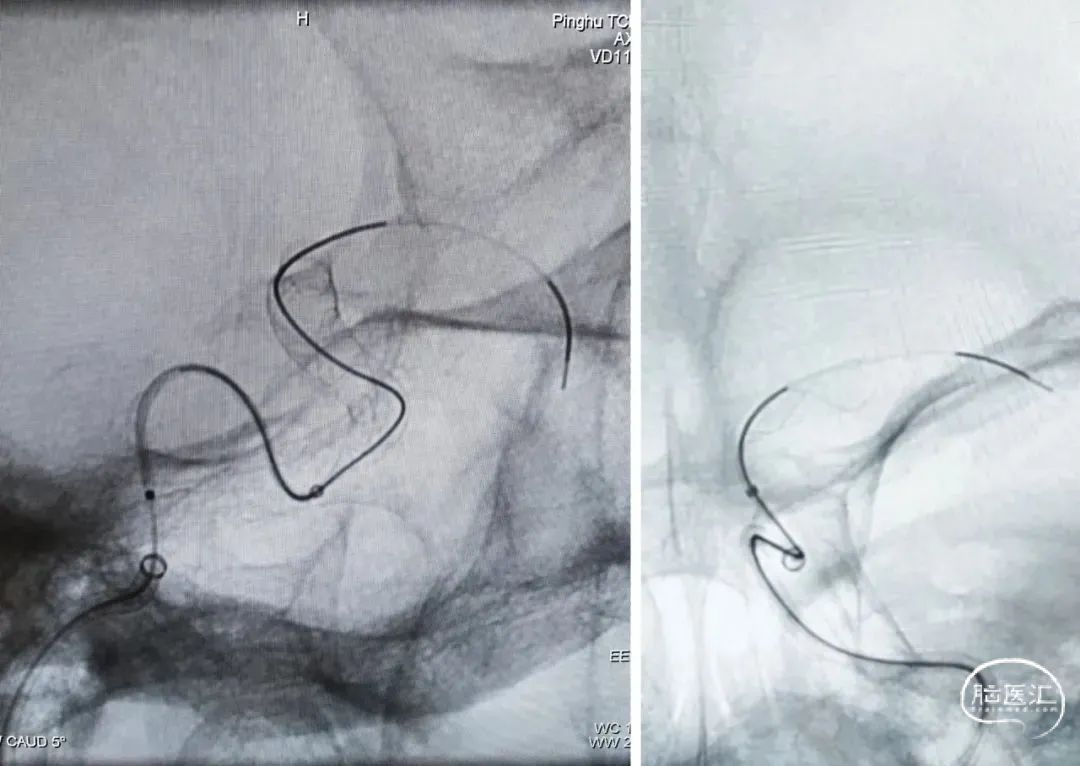

【右侧颈内动脉正位造影】

【右侧颈内动脉侧位造影】

术前诊断:右侧颈内动脉眼动脉段动脉瘤。

术前评估:右侧颈内动脉眼动脉段未破裂动脉瘤,瘤体较大、瘤颈宽,受血流冲击明显,破裂风险大。考虑到载瘤动脉条件尚可,使用血流导向密网支架治疗安全性和有效性都较理想,因此,对于此例患者拟通过血流导向密网支架植入的方式进行治疗。